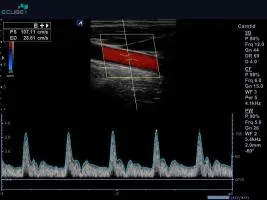

Dopplerovské ultrazvukové vyšetření

Umožňuje podrobně posoudit nález na cévním řečišti, zejména změřit rychlosti toku v jednotlivých cévách. Výsledkem vyšetření je pak posouzení cévní průchodnosti, stupeň zúžení či uzávěr cévy.

Co je to dopplerovské vyšetření?

Dopplerovské ultrazvukové vyšetření navíc umožňuje podrobně posoudit nález na cévním řečišti, zejména změřit rychlosti toku v jednotlivých cévách. Výsledkem vyšetření je pak posouzení cévní průchodnosti, stupeň zúžení či uzávěr cévy.